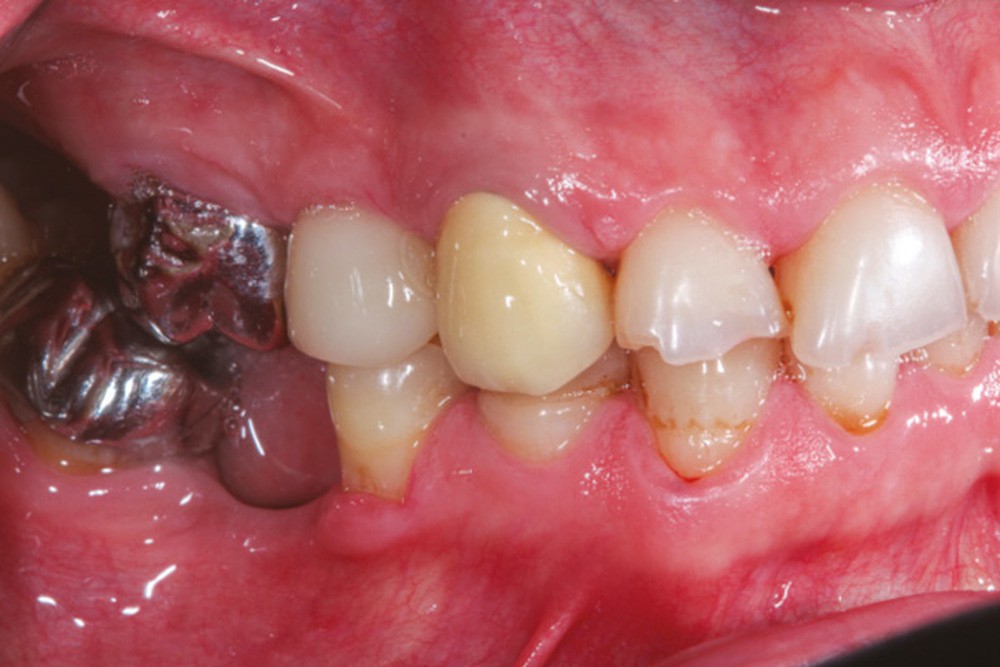

Conséquences muqueuses [11, 12]

Une extraction non compensée entraîne une vacuité de l’arcade par laquelle la muqueuse peut être « aspirée ». Il en résulte une excroissance de la joue ou de la lèvre par exemple, de forme sphérique le plus souvent. Il s’agit d’une tumeur bénigne correspondant à une hyperplasie fibro-épithéliale. Cette hyperplasie peut être retirée, mais il y aura récidive jusqu’au rétablissement de la continuité de l’arcade. Cela peut être gênant esthétiquement, mais peut aussi être à l’origine de morsures lors de la phonation ou de la mastication (fig. 20 et 21).